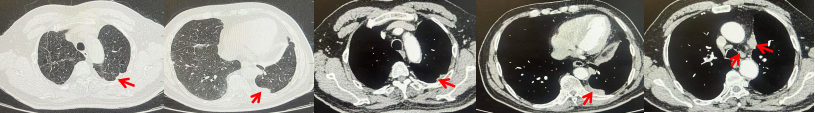

2024.09.12复查胸部CT示左侧胸膜结节,大者约为27mmx13mm,考虑转移可能性大,纵隔淋巴结增大,恶性?(如图6)。患者行胸膜穿刺活检取病理,结果示(胸膜)结合免疫组化,支持鳞状细胞癌,PD-L1(克隆号28-8)TPS约20%。分期为rT0N2bM1a IVA期,DFS为10个月。2024.09.24起行替雷利珠单抗联合紫杉醇+卡铂方案治疗4周期,复查胸CT评效SD(如图7)。后患者因脑梗塞停止治疗,于综合医院就诊,后未返院复查及治疗。

图7:替雷利珠单抗联合白蛋白紫杉醇+卡铂治疗4周期后(2024.12)胸部CT肺窗及纵隔窗